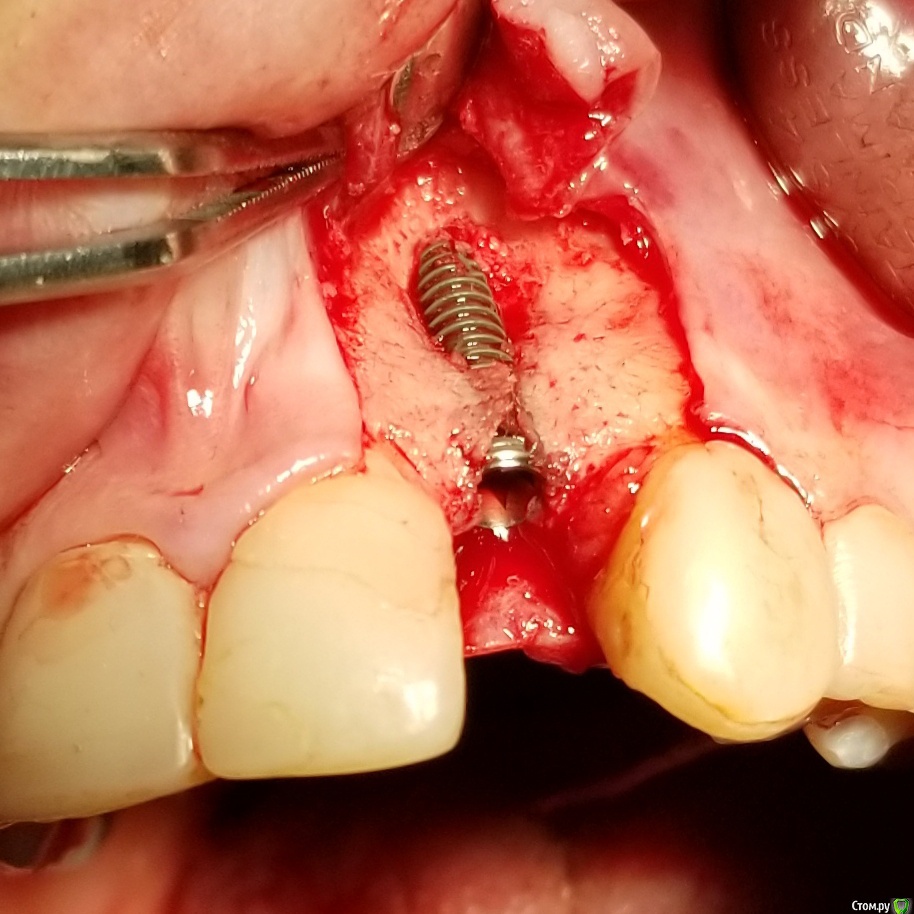

Kostoprav Опубликовано 18 сентября, 2018 Поделиться Опубликовано 18 сентября, 2018 Апатос+ ПРФ+ инъекционный ПРФ+ титановая мембрана.кт через 4,5 мес.Честно говоря кости ожидал побольше, так как паковал с гиперобобьемом. Ссылка на комментарий

stommm Опубликовано 20 сентября, 2018 Поделиться Опубликовано 20 сентября, 2018 Имхо для такого дефекта лучше сетку подлиннее (у нео есть такие) что бы апекально фиксировать в кости, а не так что апекальный край сетки лежит над дефектом. И Имплант по фото недогазлублен. Либо профиль неудачный будет, либо коронка короткая. При бОльшем заглублении имхо получилось бы лучше Ссылка на комментарий

Kostoprav Опубликовано 20 сентября, 2018 Автор Поделиться Опубликовано 20 сентября, 2018 Имхо для такого дефекта лучше сетку подлиннее (у нео есть такие) что бы апекально фиксировать в кости, а не так что апекальный край сетки лежит над дефектом. И Имплант по фото недогазлублен. Либо профиль неудачный будет, либо коронка короткая. При бОльшем заглублении имхо получилось бы лучше имплант с полированой шейкой, эго не желательно сильно погружать под кость.В инструкциях производителя этот тип мембран не предназначен для апекальной фиксации, есть мембраны с проререзями под винты но у нас таких не продают. Ссылка на комментарий

АнтонТЛТ Опубликовано 20 сентября, 2018 Поделиться Опубликовано 20 сентября, 2018 имплант с полированой шейкой, эго не желательно сильно погружать под кость.В инструкциях производителя этот тип мембран не предназначен для апекальной фиксации, есть мембраны с проререзями под винты но у нас таких не продают.Только шейка не полированная, а фрезерованная. Мембраны с прорезями это более новый вид. Мембраны без прорезей можно пробивать пином или пин/винт крепить между ножек. В вашем случае, если не прибивать, то надо было мембрану лучше загнуть или взять больший размер, чтобы мембрана опиралась на кость апикально. 2 Ссылка на комментарий